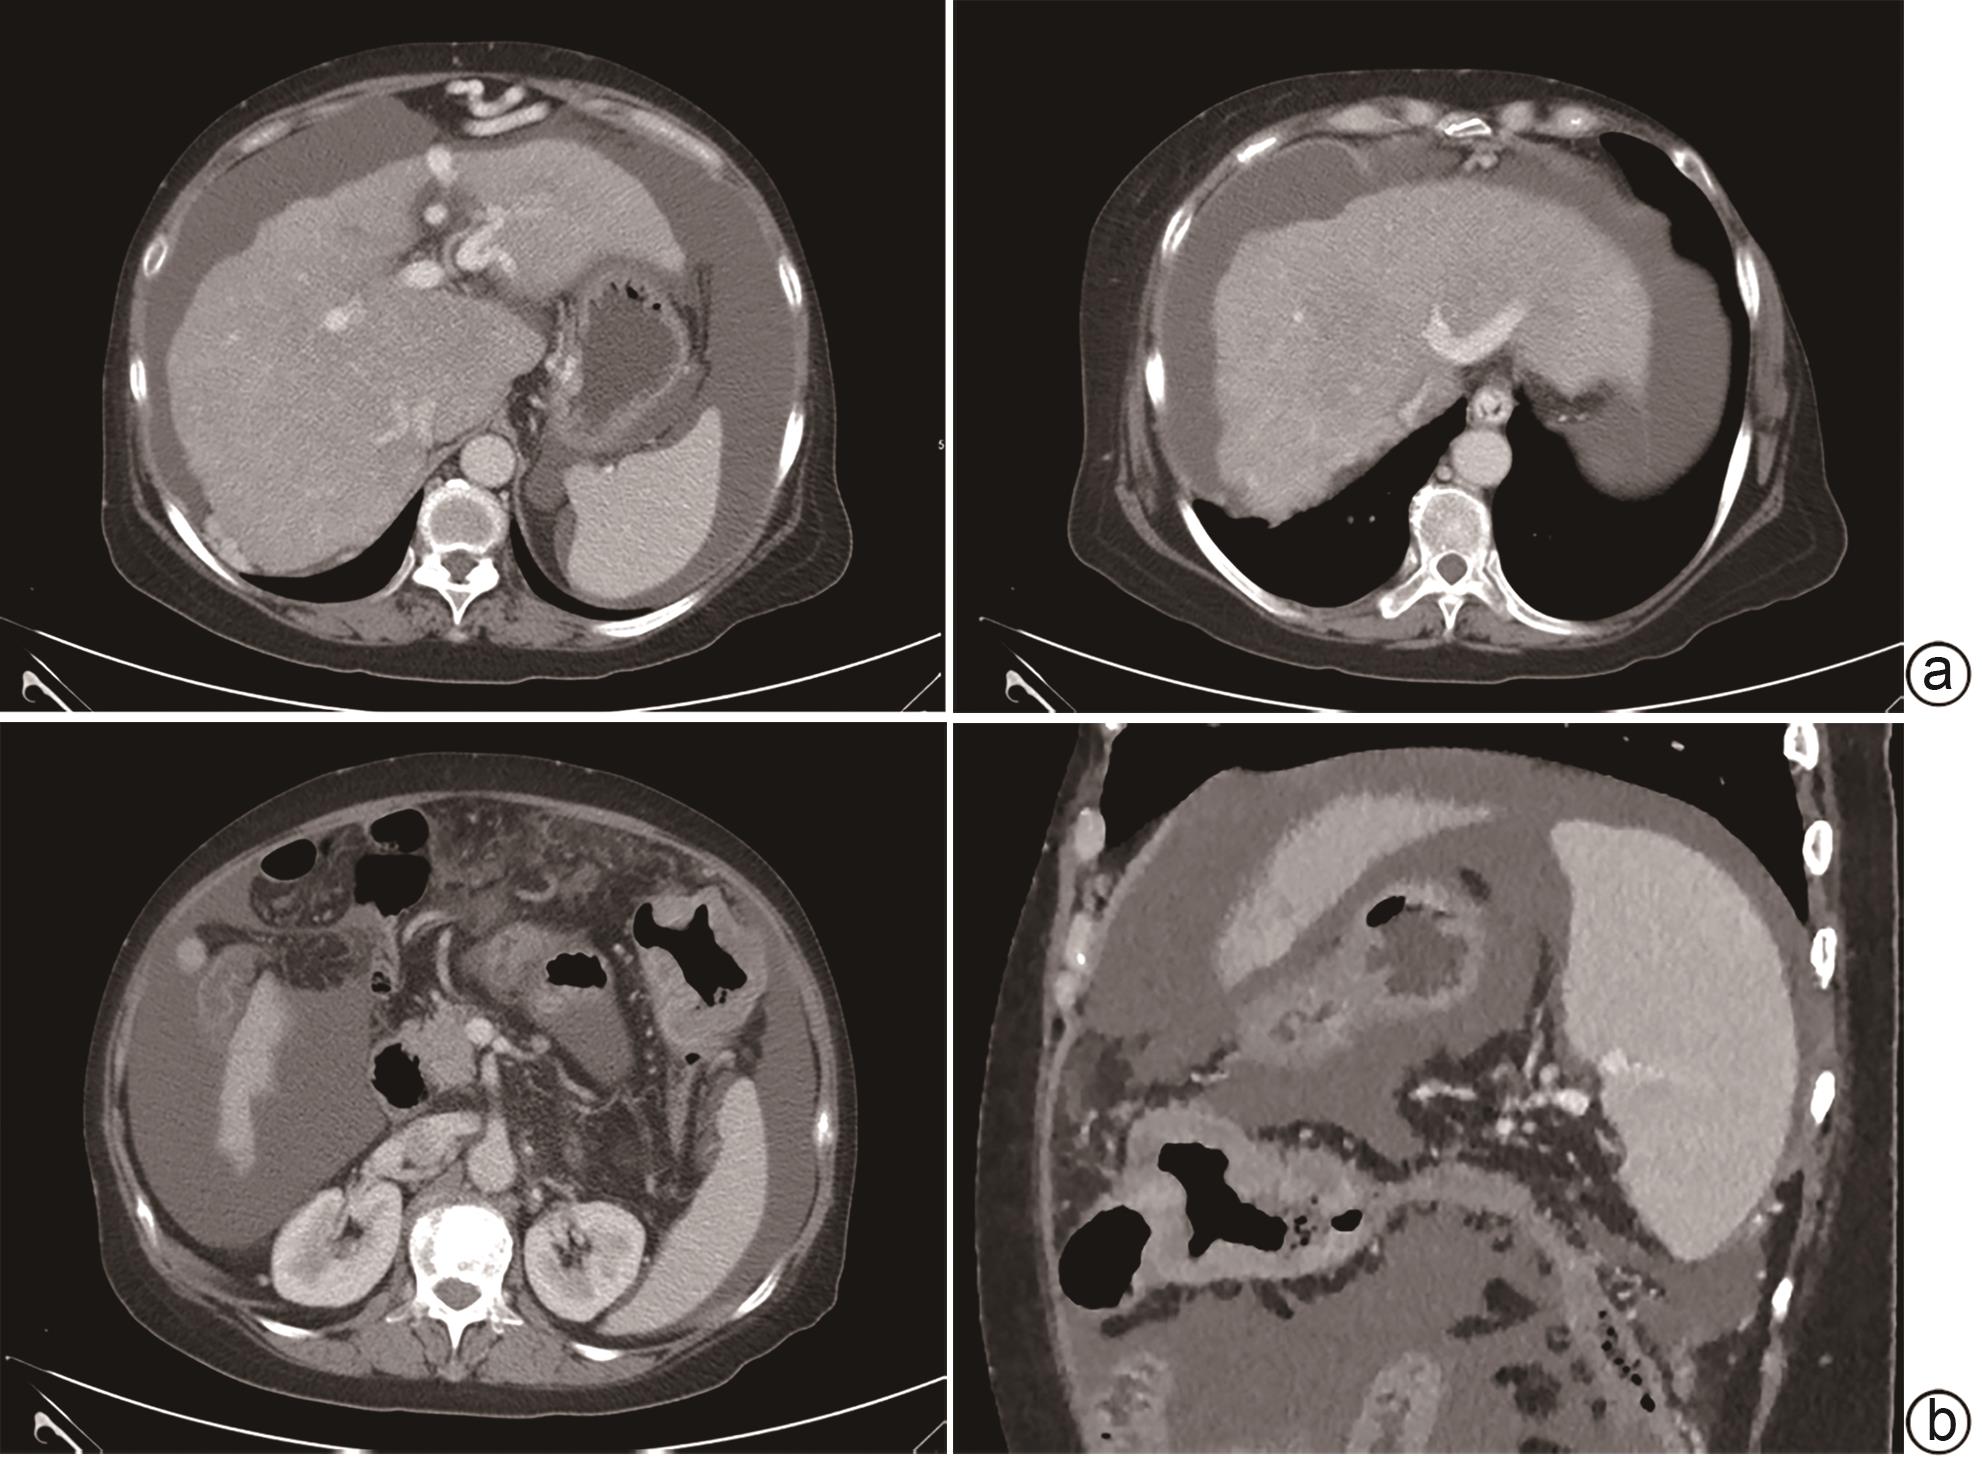

Case Report

Diagnosis and treatment of decompensated cirrhosis with multiple primary cancers: A case report

Wenting CHAO, Rui HUANG

2024, 40(9): 1868-1872. DOI: 10.12449/JCH240923

Abstract(927) HTML (392) PDF (1776KB)(108)

Abstract:

Multiple primary cancers (MPC) refer to the presence of more than one type of cancer with different histological features and sites in the same individual, and it is relatively rare in clinical practice. This article reports a case of decompensated cirrhosis with MPC and discusses the diagnosis, treatment, and clinical implications of this patient with decompensated cirrhosis and MPC.